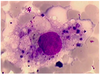

Expliquez cette image

Passage des globules blancs (leucocytes) du vaisseau vers le milieu extra-vasculaire endommagé.Le fibrinogène,protéine soluble, se polymérise en fibres insolubles (fibrine), emprisonnant les bactéries et servant de support aux leucocytes.